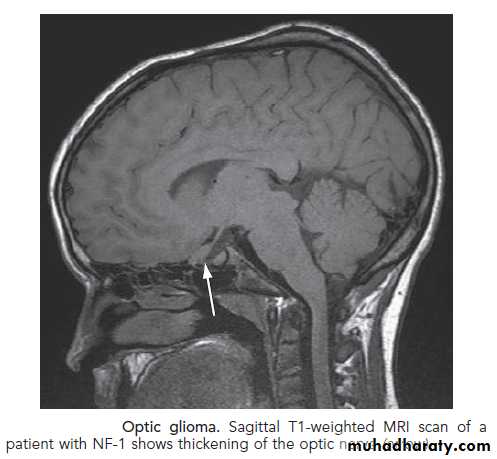

5. Optic gliomas.

Neuroimaging study